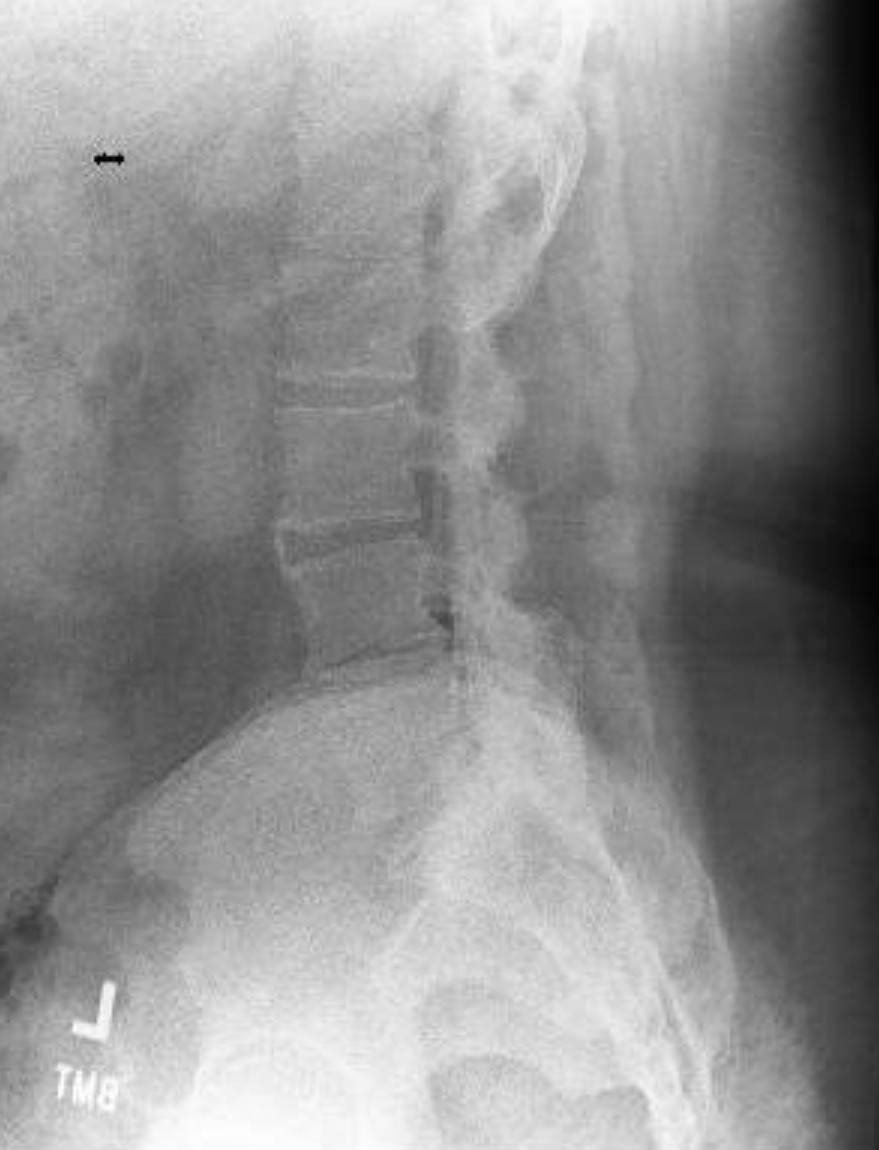

On top of the dental issue, I’m also dealing with Lumbar Spondylosis and Degenerative Disc Disease. My spine has a curvature to the right, with narrowing and arthropathy in the lower lumbar area. Recently, I also bruised my spine, which has made movement — and working — almost impossible.